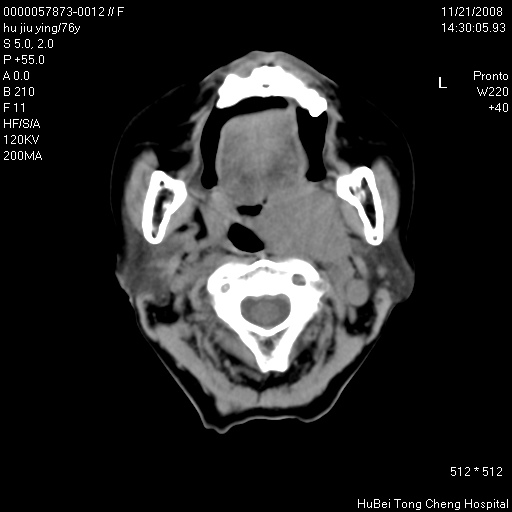

患者 女,76岁。左颈部包块20余天。pe:左侧扁桃体ⅲ度肿大,表面不平,有新生血管,右咽柱红肿,无溃疡。左颈上部包块约3cm×4cm大小,质中等,压痛,边界不清,不能移动。

临床诊断:左侧扁桃体肿瘤?

咽部及颈部ct轴位平扫(层厚、层距均为5mm),图像如下:

左侧咽旁软组织密度肿块影,形态不规则,与周围结构分界欠清,性质待定,建议增强;另双侧上颌窦炎.

支持:1)左侧扁桃体肿瘤;

2)双侧上颌窦炎症.